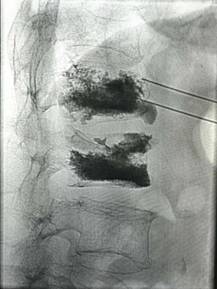

椎间孔镜微创术治疗腰椎间盘突出症

优点:损伤小、恢复快。

2、脊柱手术微创化理念:采用椎间孔镜等脊柱微创手段实施各种脊柱微创手术。治愈了大量的腰间盘突出症、腰椎管狭窄症、颈椎病患者。采用PVP、PKP术治愈了大量高龄脊柱压缩性骨折患者,近年来累计完成4000例该微创手术。60%的脊柱病人可以进行微创手术,具有创伤小、效果好、安全性高、恢复快、术后不需长期卧床等特点。微创手术保持极高的优良率与可靠性。脊柱微创技术居于淮海经济区先进水平。我院在淮海经济区率先开展颈椎微创手术。